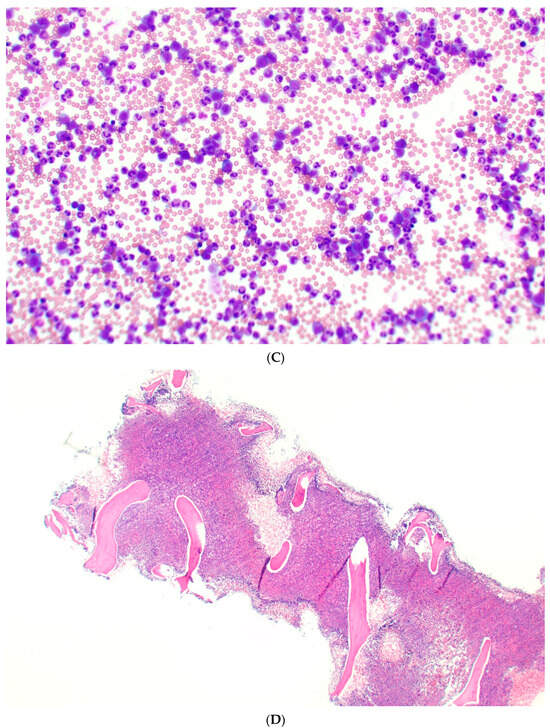

3.2.1. Peripheral Blood

3.2.2. Bone Marrow